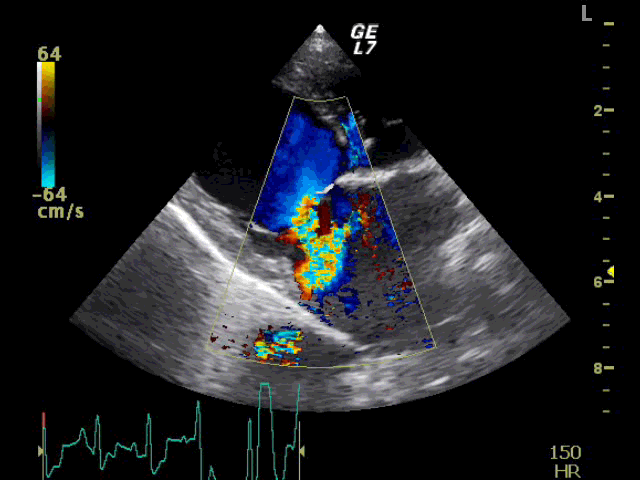

循環器科:僧帽弁逆流の動画